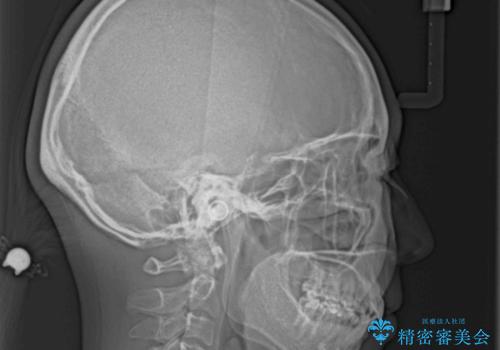

ふっくらとした口元を改善したい 目立たないワイヤー装置による抜歯矯正

- 前歯のデコボコを気にして来院された患者様です。

当初は口元の突出感はあまり気にされていない様子だったので、インビザラインによる非抜歯矯正をお勧めしたが、ふっくらとした口元を改善したいとのことで、積極的に口元の突出感を改善することとしました。

上下左右第一小臼歯4本の抜歯を行い、ワイヤー装置による矯正治療を行うこととしました。

元々上下正中の位置はずれていましたが、治療中によりズレが大きくなったので、元の位置に戻すため治療期間を余計に要しました。

横顔の印象が大きく改善され、患者様には大変満足していただきました。